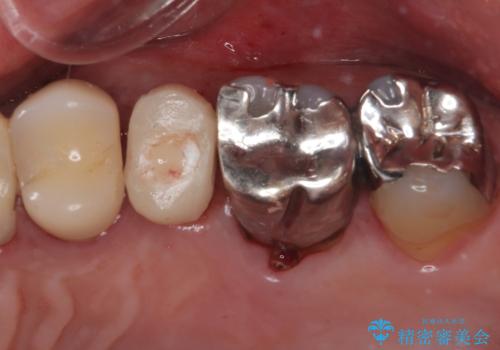

抜歯と同日にインプラントを埋入し、さらに仮歯まで装着するため、治療当日から見た目と噛む機能の回復が可能です。治療期間中も審美性と日常生活の快適さを維持できます。

抜歯即時インプラント後、治癒期間を経て、約3か月でセラミックによる最終補綴が完了しました。